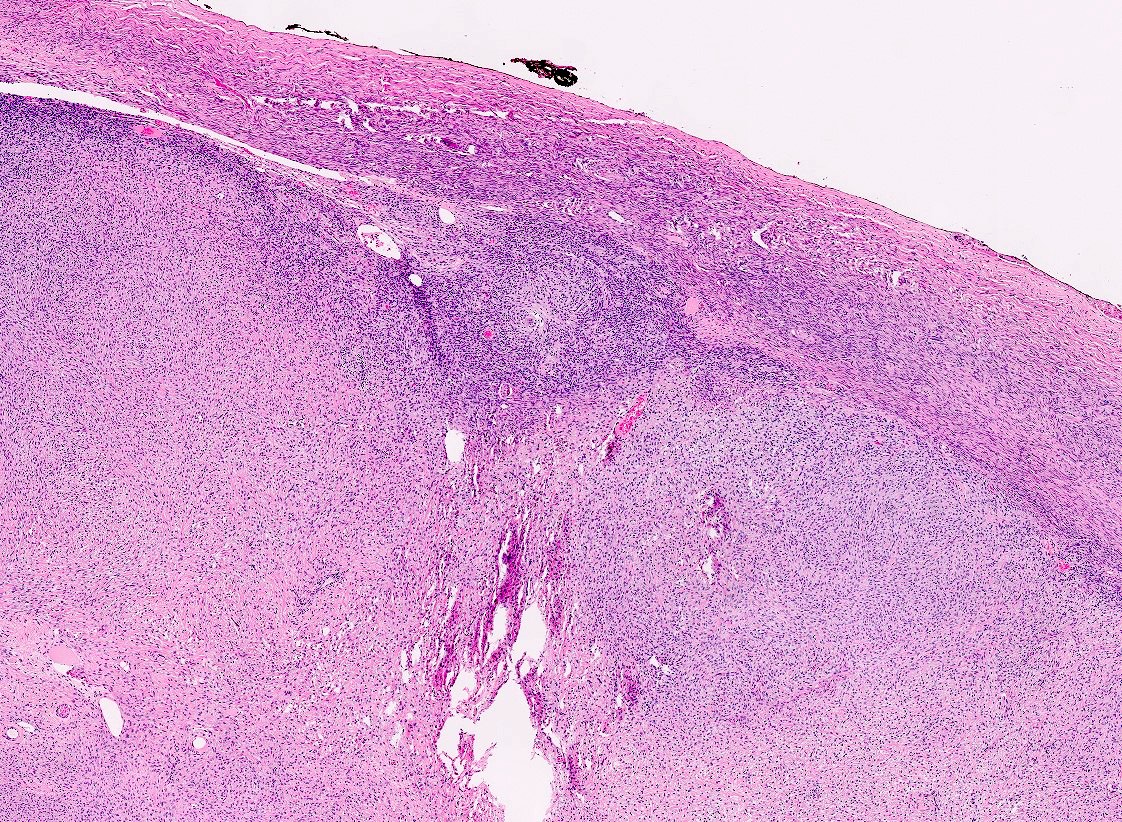

Microscopic (histologic) description

- Predominant population of cells showing ovoid to round nuclei and pale gray cytoplasm, which can be abundant

- Minor component of the tumor may have spindled nuclei, reflecting overlap between fibroma and thecoma

- Indistinct cell membranes impart a syncytial appearance

- Diffuse or nodular growth pattern

- Absent or minimal nuclear atypia

- Mitotic rate usually < 5/10 high power fields

- Hyaline plaques

- Cytoplasmic lipid vacuoles may be present but are not essential

- May show aggregates of cells with brightly eosinophilic cytoplasm (lutein cells)

- Calcification is more common in young patients (Int J Gynecol Pathol 1988;7:343)

- Uncommon features include keloid-like sclerosis, nuclear grooves, bizarre nuclear atypia (Am J Surg Pathol 2014;38:1023)

- Rarely contains a minor component of sex cord elements (Int J Gynecol Pathol 1983;2:227)

- Malignant thecoma: very rare, diagnosis requires diffuse moderate to severe nuclear atypia and high mitotic rate (> 4/10 high power fields) (Am J Surg Pathol 2011;35:e15)

Microscopic (histologic) images

Contributed by Victoria Collins, M.D., Tamara Kalir, M.D., Ph.D., AFIP and @SeoparjooAzmel on Twitter